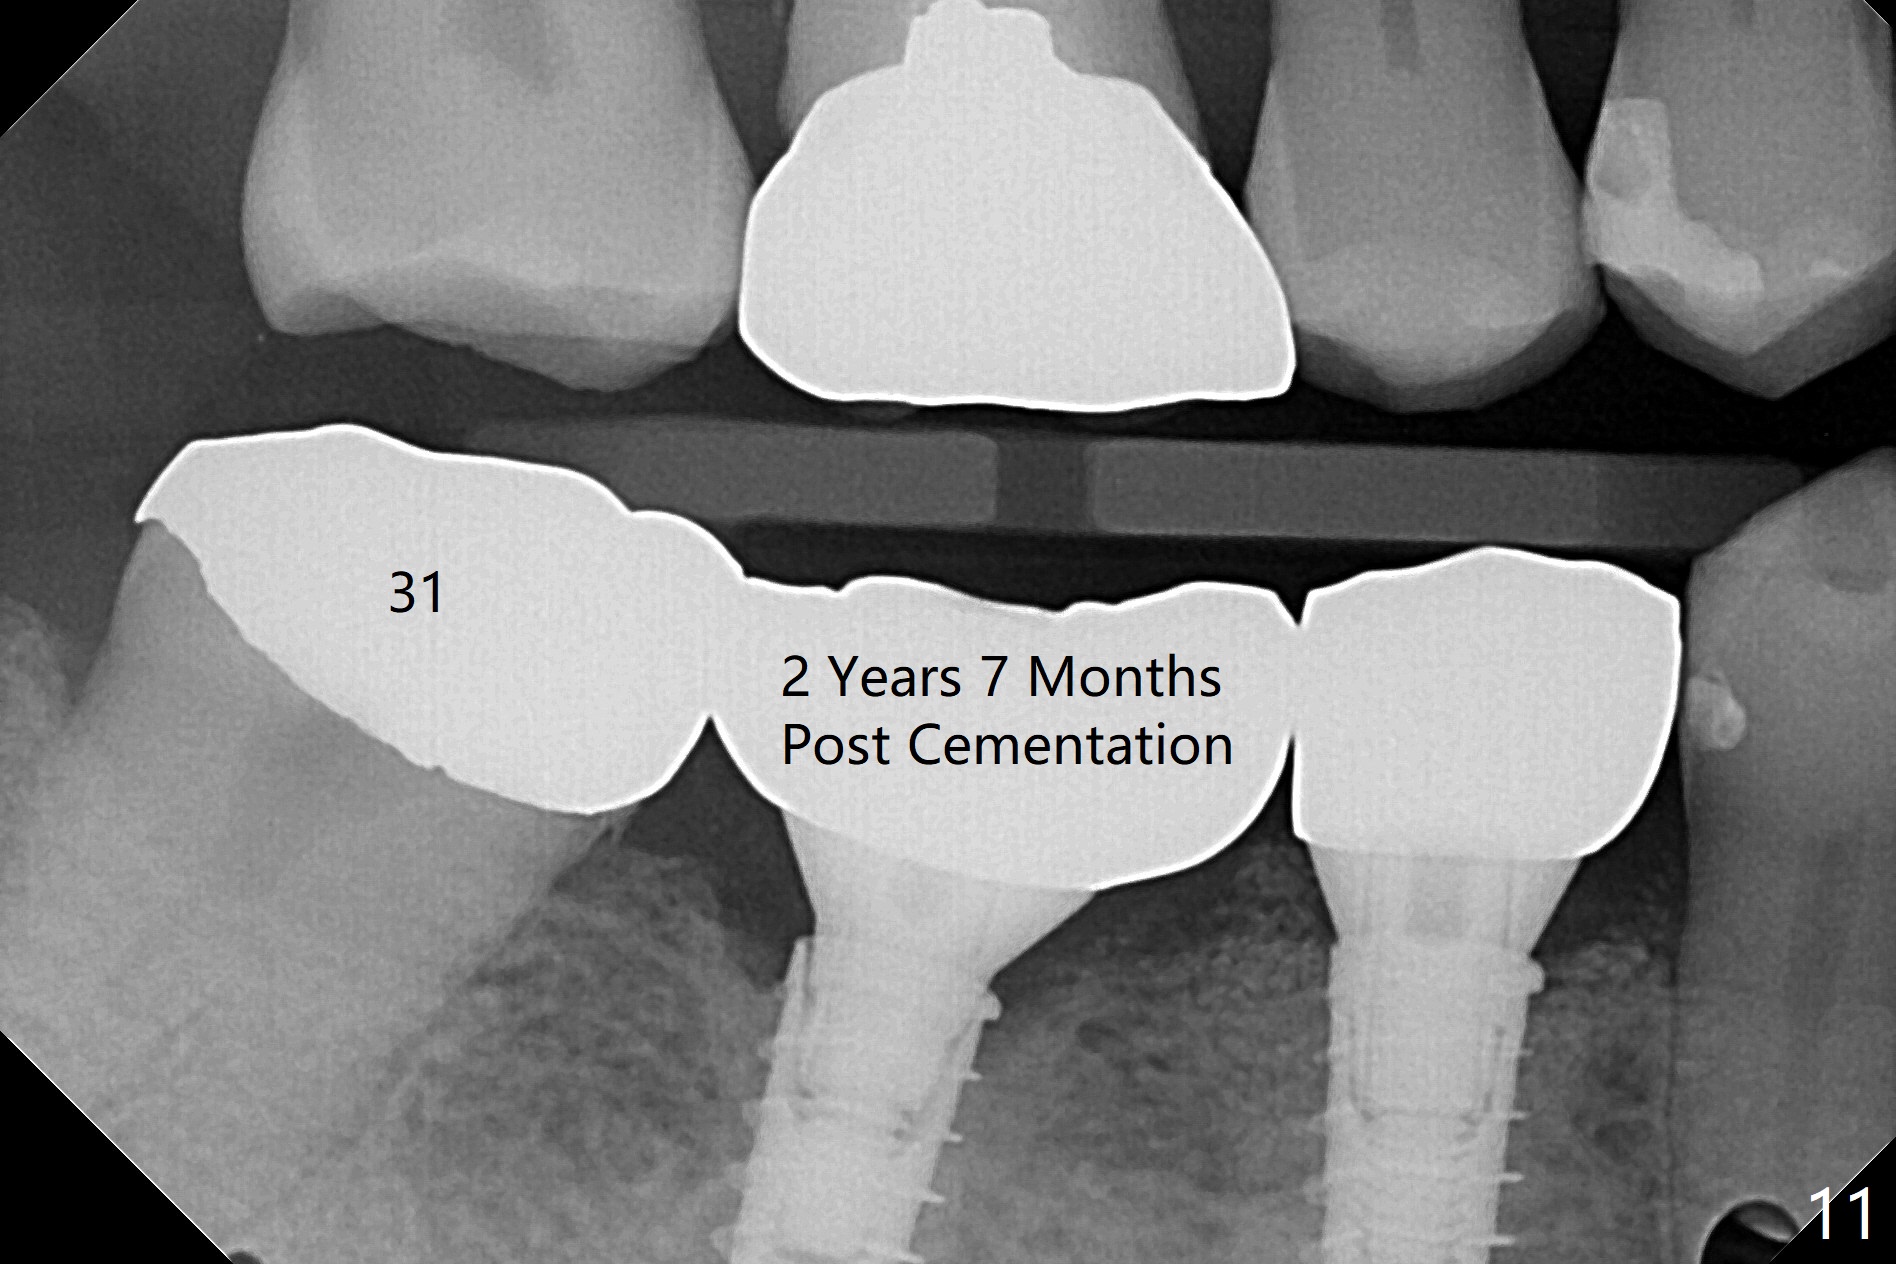

After incision, the ridge at #29 and 30 is found ~ 5 mm wide buccolingually. To place a 4x11 mm IBS implant at #30, the ridge is expanded using BEB technique (bone expansion and bending, Fig.1). It appears that the initial osteotomy at #29 is mesial (Fig.1 yellow dashed line: the distal surface of the root of the tooth #28). After moving the osteotomy distal, the final implant position at #29 (4x11 mm) is within normal limit (Fig.2). The bone at #29 seems to be not so dense that bending (using 1.6 mm drill) is not necessary (using Magic Split and Magic Expanders 3 and 3.8 mm). Later the implant at #30 (4x11 mm) is placed deeper (Fig.3). After placing bone graft around the implants/abutments and suturing, the ridge looks wider with apparent formation of the gingival bands around the abutments (Fig.4 *). Three months and a half postop, bone loss is minimal (Fig.5) and gingival bands forms around the abutments (Fig.6). Fig.7 is taken 1 month post cementation (panoramic X-ray). The patient chews normally 1 year (Fig.8) and nearly 2 years (Fig.9,10) post cementation. The crown at #31 needs recementation 2 years 7 months post #30 cementation; the incomplete seating of the abutment was noted for the first time (Fig.11). Five months later the patient is going to be retired and wants to travel abroad. After approval, the access hole was reopened; articulating paper shows under occlusion of the crown (Fig.12). Since the gap between the abutment and the implant is large, the abutment/crown complex seems to be necessary to be turned (Fig.13 curved arrow). The proximal surfaces of the crown need to be trimmed (straight lines). After turning, the crown sits down with screw tightening; the patient feels pain from the gingival cuff (Fig.14). After turning, the abutment appears to be completely seated (Fig.15). In fact the mesial and distal surfaces of the crown should have clearance from the neighboring teeth (Fig.14) so that pick-up impression is able to hold the crown/abutment complex securely (Fig.16: *). The crown is separated from the abutment after crown repair. They are seated together (loose connection) using the crown as a guide to seat the abutment. BW is taken without the crown. It appears that the abutment remains seated completely (Fig.17). The apical space is equal between #29 and 30 (Fig.17, as compared to Fig.5).